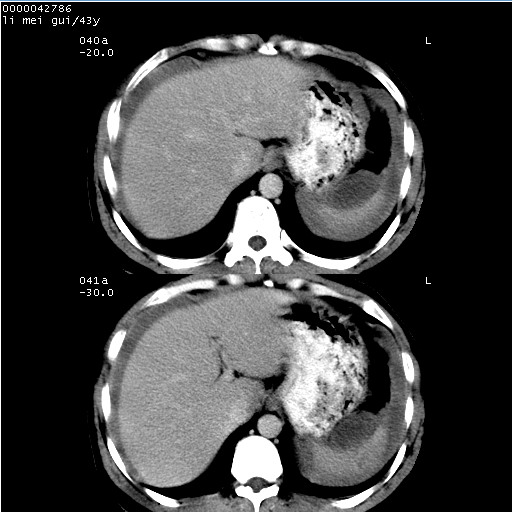

| 患者,男,43岁。突发腹痛2小时,面色苍白,难以平卧。自述近期无明确外伤史,为摩托车驾驶员。 腹部b超检查:脾脏中上极回声异常,肿瘤待排。 临床诊断:腹痛原因待查。 上中腹部ct轴位平扫+增强扫描(层厚10mm,螺距1.0,重建间隔10mm),图像如下: ![]() ![]() ![]() ![]() ![]() ![]() ![]() ![]() ![]() ![]() ![]() ![]() ![]() ![]() ![]() ![]() ![]() ![]() ![]() ![]() ![]() ![]() ![]() ![]() ![]() ![]() ![]() ![]() ![]() ![]() ![]() ![]() ![]() ![]() ![]() zrs发言:支持脾破裂 wwp发言:支持脾破裂并腹水。 xulianj发言:脾脏肿瘤破裂可能性大 zsl6918发言:不像肿瘤出血,考虑还是与外伤后引起的慢性出血有关 zzyy发言:平扫见肝周及脾周积液,脾内密度不均。脾内肿瘤较少见。还是外伤性脾破裂。 沈丘东方医院发言:脾门区一个不均匀强化病灶与其周液体相连多考虑脾占位破裂出血 yixianman001011发言:脾破裂并腹水是可以肯定的,具体原因多以肿瘤性破裂出血,脾脏淋巴瘤可能性大. 结果: 术后,经详细询问患者,其仔细回忆:一月前骑摩托时左侧腰部与别人有“轻微”触碰,因责任在自已,当时又无明显不适,未引起注意。 临床术后诊断:脾破裂并失血性休克(1.外伤性迟发性脾破裂。2.脾脏肿瘤破裂?) 术后标本病检:脾破裂并出血,未见明显肿瘤成份。 原贴地址:http://www.radinet.com.cn/forum_view.asp?forum_id=4&view_id=34070 |